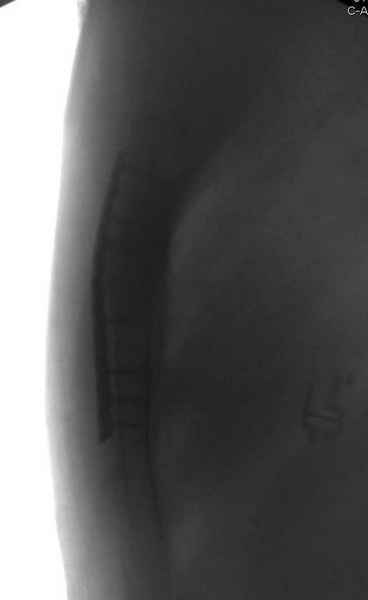

Вложение не в текстовом формате было извлечено…

Имя     : 3 Nonunion sternum ap.jpg

Тип     : image/jpeg

Размер  : 32563 байтов

Описание: отсутствует

Url     : http://weborto.net:8080/pipermail/ortho/attachments/20090403/0de56d8e/attachment-0012.jpg